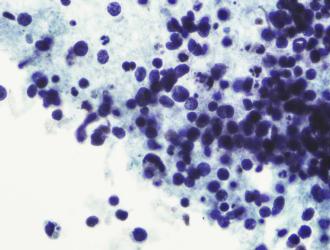

Il tumore del polmone è la prima causa di morte per cancro, responsabile di circa un terzo dei decessi per malattie oncologiche.

«Il tumore non a piccole cellule rappresenta l’85% delle diagnosi di tumore al polmone e al momento le opzioni terapeutiche sono limitate», spiega Elena Levantini...